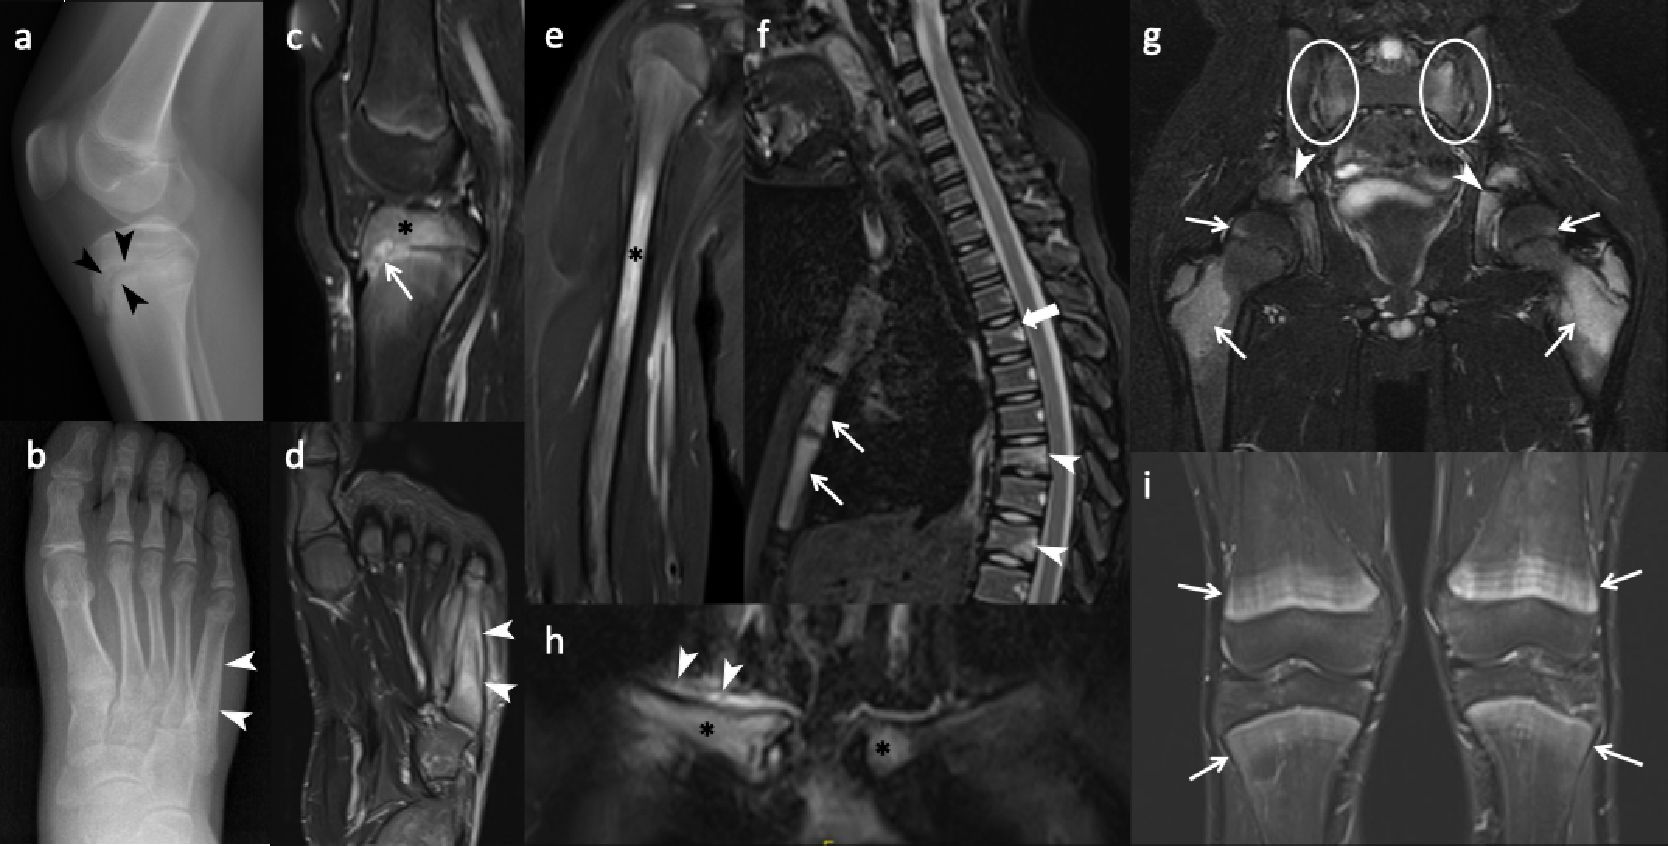

Radiographs and CT reveal round or ovoid osteolytic bone lesions centered at physeal lines which extend to both epiphysis and metaphysis of long bones (Fig. 3a). Sclerotic changes develop subsequently, progressing to hyperostosis and bony expansion, accompanied by a smooth or lamellated periosteal reaction in persistent chronic lesions (Fig. 3b). However, radiographic findings may be occult or normal at the early or healing phases of the disease.11,33

In addition to the initial work-up, radiographs are essential for follow-up of complications. Due to physitis, early physeal closure may occur through the formation of a physeal bridge or bar. Radiographs can demonstrate the characteristic “physeal tongue,” which appears as a lytic or sclerotic tubular structure extending toward the metaphysis. Another point in follow-up imaging is treatment associated findings in patients who were treated with cyclic bisphosphonates (e.g., pamidronate), including fine sclerotic lines in the metaphysis known as zebra stripes, resulting from inhibited osteoclast activity.39

Magnetic resonance imaging

Whether focused or encompassing the whole body, CNO presents several unique characteristics on MRI. The hallmark of CNO on MRI is physitis related periphyseal osteitis that appears as hyperintense foci on fluid sensitive sequences (STIR or T2-weighted fat-saturated) and hypointense foci on T1-weighted images (Fig. 3c). Periosteal reaction, surrounding soft tissue edema and reactive synovitis may accompany the osteitis (Fig. 3d).54 Lesions more commonly locate at the metaphysis or epi-/apophysis of a long bone (Fig. 3c). Diaphyseal involvement is less common (Fig. 3e). In flat and round bones, lesions affect the epi- or metaphyseal-equivalent regions of each bone that are in close proximity to the growth plates (i.e., apophyses of the iliac bones, endplates of the vertebrae, bones surrounding sacroiliac joints, Y-cartilage, ischiopubic synchondrosis) (Fig. 3f, 3g).11,54 Pelvic bones including the proximal femurs and sacroiliac joints are the most commonly involved regions across the body. Long bones of the lower extremity (lower legs and feet > bones around the knee), upper extremities, and vertebral bodies are other sites that are usually involved in descending order. The clavicle, sternum, scapula, and mandible are other involved body parts (Fig. 3h).39 In the spine, the thoracic and sacral vertebrae are the most commonly involved sites and osteitis is usually located focally at the superior endplate of the vertebra.39,55 More importantly, the spine is the commonest site of pathological fracture in CNO and as high as half of cases with spinal disease resulted in vertebral deformities such as vertebra plana or scoliosis (Fig. 3f). 33

After treatment, osteitis foci may fully resolve or heal with sclerosis. Vertebral height loss may persist without osteitis as a marker of previous disease. A diagnostic pitfall after bisphosphonate treatment is the presence of bilateral symmetric bright metaphyseal bands on STIR. These high-signal bands can mimic disease relapse, and their abrupt demarcation in relation to the adjacent metadiaphysis can be a key feature for differentiating them from true osteitis (Fig. 3i).54

CNO mimickers

Normal variants of bone marrow, such as red marrow in the metaphysis during childhood and residual red bone marrow foci in the feet, should not be misinterpreted as osteitis (Fig. 4d). Focal periphyseal edema (FOPE) is another incidental finding located around the physis during the physeal closure period (Fig. 4a). Bone contusions, physeal stress injuries, stress fractures, or reactions may result in or associated with osteitis, but history of trauma—either acute or chronic—and the location of these lesions can help differentiate them from CNO (Fig. 4b, 4c). Hematogenous osteomyelitis can also mimic osteitis in CNO, but in addition to the patient’s history, physical examination, and laboratory findings, the presence of an abscess inside the bone and surrounding soft tissue, heterogeneous enhancement of bone marrow, and localized disease (as opposed to multifocal lesions) can aid in differentiation between these two entities (Fig. 4d, 4e). Neoplastic, infiltrative, or metastatic bone lesions, such as Ewing sarcoma, Langerhans cell histiocytosis, and leukemia, can pose diagnostic challenges; however, factors such as the patient’s age, the presence of an extraosseous solid soft tissue component of the tumor, abrupt lesion contour, and lesion location and shape are key features to consider when evaluating these pathologies (Fig. 4f‒h). Scurvy, as a metabolic condition, is another mimicker that presents with metaphyseal osteitis. However, subperiosteal hemorrhages are not seen in CNO (Fig. 4i).33,54